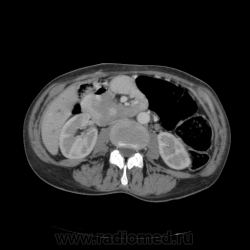

КТ ОБП - гепатомегалия, признаки панкреатита

МРТ ОБП - от 16.12.10 гепатомегалия, расширение панкреатических протоков.

Похоже на то, что все было списано на калькулезный холецистит. Наши морфологи пересмотрели стекла с гистологией и окончательно написали о наличие высокодефференцированной аденокарциноме. У меня только две мысли образования исходит из БДС или первичный рак 12п.к., хотя сейчас гадать бесполезно. 12п.к. циркулярно сужена.